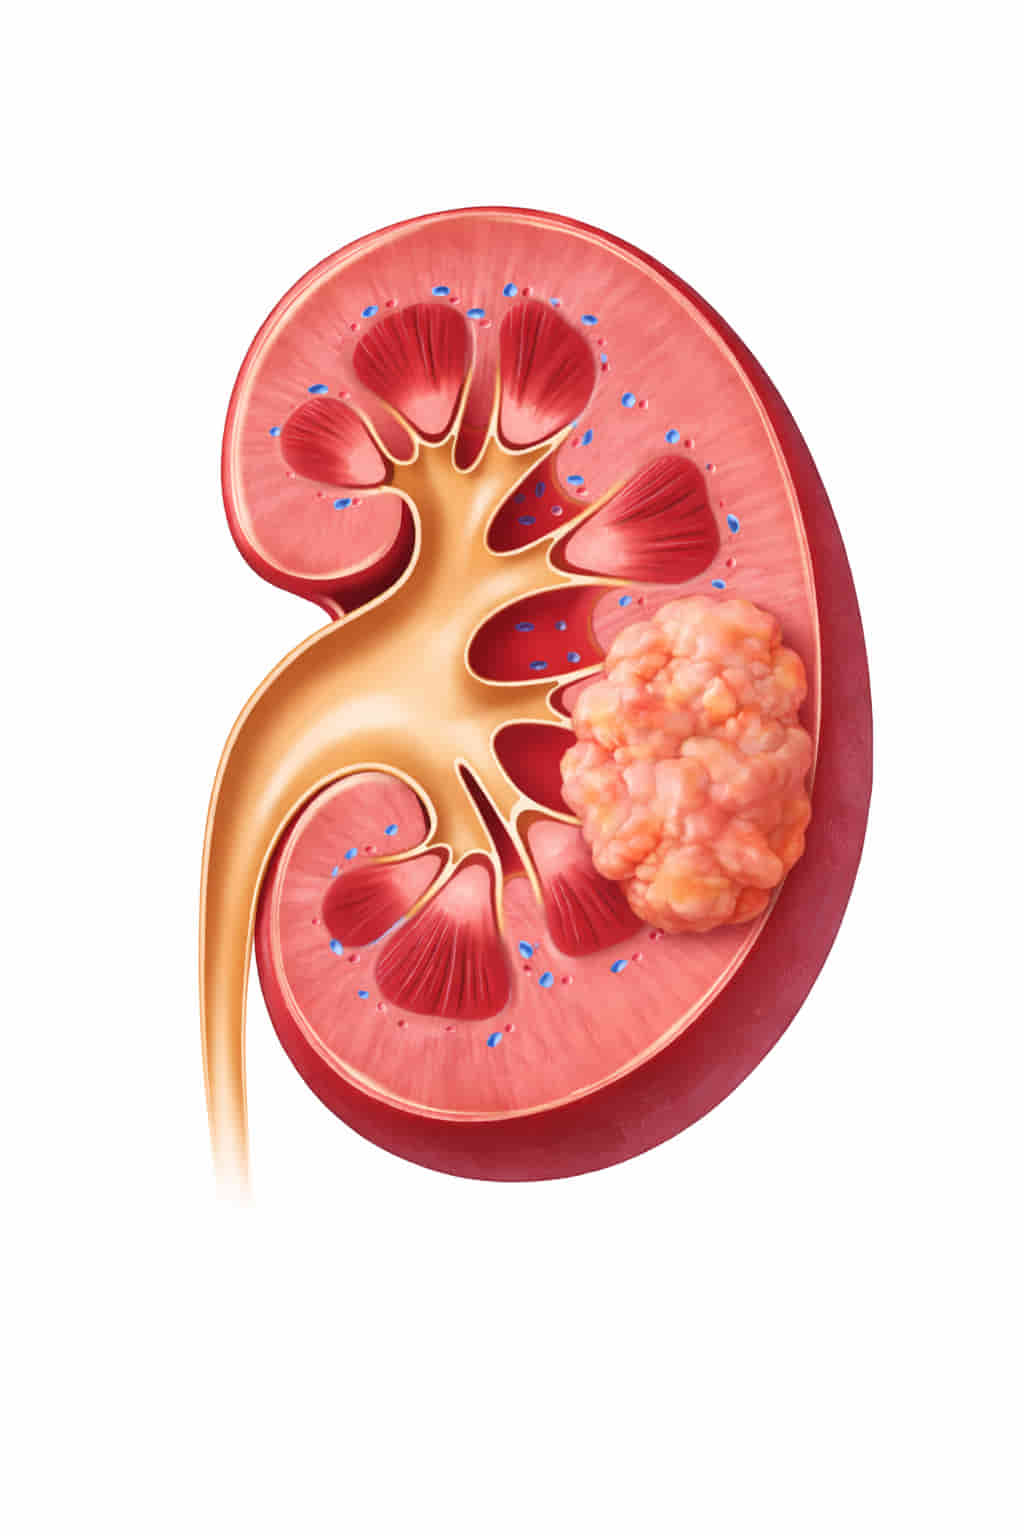

Understanding Kidney Tumors and When Minimally Invasive Treatment Is Needed

Many kidney tumors are found unexpectedly during scans done for other health problems. Some patients may notice symptoms like:

- blood in the urine.

- side pain.

- but often the tumor causes no warning signs.

- removing the entire kidney or undergoing major surgery may not always be necessary.

For patients who want to preserve kidney function or avoid a long recovery, minimally invasive treatments like Renal Cryoablation provide a safe and effective option—destroying the tumor while protecting the healthy part of the kidney.

For patients diagnosed with small kidney tumors, traditional surgery to remove part or all of the kidney is no longer the only option.

Renal Cryoablation is a cutting-edge, minimally invasive treatment that uses extreme cold to destroy cancerous cells while leaving the healthy part of the kidney intact.